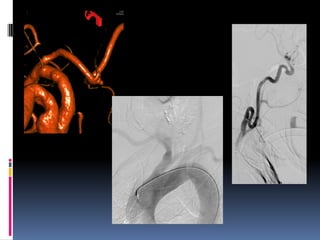

Parent vessel occlusion-Cavernous ICA, dissecting (VA), small peripheral

Fusiform, dissecting aneurysm

Parent vessel occlusion-CavernousICA, dissecting (VA), small peripheral